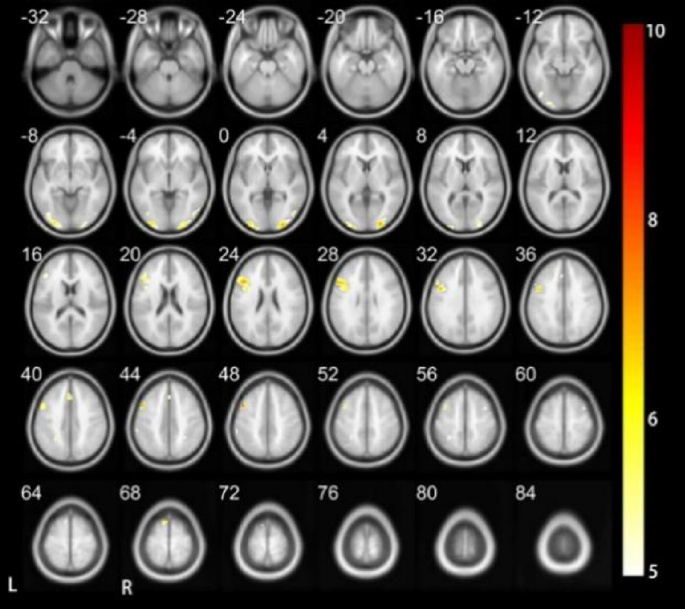

The presentation of data from Figs. 6 and 7; Tables 6 and 7 elucidates the neural activation patterns observed during the execution of the Vocal Tone 3 Task in DC compared to HC. This comprehensive analysis reveals intricate differences in brain activation that highlight the unique neural strategies employed by deaf children in processing complex tonal sequences. In DC, a wide array of regions were activated. The right supplementary motor area, left precentral gyrus, right triangular inferior frontal gyrus, right insula (part of the inferior frontal gyrus), right middle frontal gyrus, bilateral superior temporal gyrus, left insula, left middle occipital gyrus, and left temporopolar area of the superior temporal gyrus are included. Additionally, the bilateral middle occipital gyrus, right medial occipital gyrus, left triangular part of the inferior frontal gyrus, left superior medial frontal gyrus, left supplementary motor area, and left medial parietal lobe were engaged during the task. These regions are involved in motor planning and coordination, language processing, auditory processing, and visual information integration.

Comparatively, in DC, there was noted activation in regions such as the left precentral gyrus, right insula (part of the inferior frontal gyrus), right middle frontal gyrus, bilateral superior temporal gyrus, left insula, and left temporal pole of the superior temporal gyrus. These regions are not activated in HC. Conversely, the medial occipital gyrus, left superior medial frontal gyrus, and left medial parietal lobe showed activation in HC but not in DC. Interestingly, while DC exhibited activation in the left hemisphere of the middle occipital gyrus, their hearing counterparts demonstrated bilateral activation in this region. Furthermore, the patterns of activation in the deltoid inferior frontal gyrus and supplementary motor area were hemisphere-specific. DC showing right hemisphere activation, in contrast to the left hemisphere activation observed in HC.